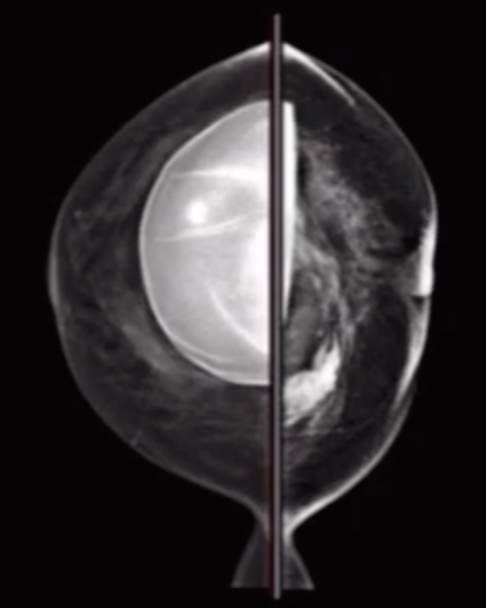

Radial Fold

• Basically the normal folds in the capsule of the breast implant

• Mimics rupture